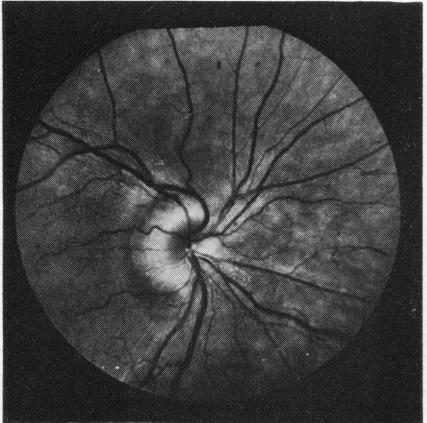

倾斜的视盘

The tilted disc.

Sixty tilted discs were studied by colour photography, including some by fluorescein angiography. Attention was drawn to the contracted, D-shaped outline of the scleral canal, and it was suggested that fewer fibres than normal enter the defective side of the disc. This was supported by examination of the nerve fibre layer and the discovery of field defects in 13 of the 27 eyes in which the visual fields were examined. The similarity of these features with congenital hypoplasia of the optic nerve head was noted.

通过彩色摄影对60个倾斜视盘进行了研究,其中一些还进行了荧光素血管造影。人们注意到巩膜管呈收缩的D形轮廓,并提出进入视盘缺陷侧的纤维比正常情况少。对神经纤维层的检查以及在接受视野检查的27只眼中的13只眼中发现视野缺损支持了这一观点。还注意到这些特征与视神经乳头先天性发育不全的相似性。